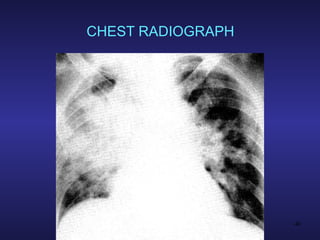

CLINICAL FEATURES PULMONARY Common association with ARDS Lung edema resulting from increased alveolar-capillary permeability Dyspnea & hypoxemia Noncompliant “heavy” lungs Bilateral pulmonary infiltrates Abnormal opacities on CXR

CHEST RADIOGRAPH